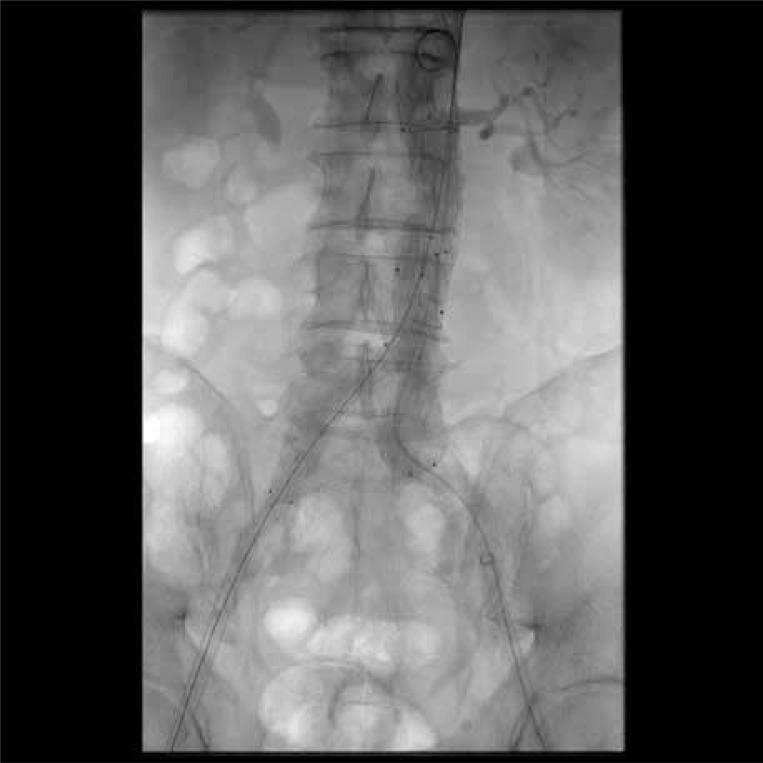

低轮廓与标准轮廓支架型人工血管治疗腹主动脉瘤的病例匹配研究

Low-profile versus standard-profile stent grafts in the treatment of abdominal aortic aneurysm: a case-matched study.

Endovascular aortic repair (EVAR) is nowadays a widespread method of managing abdominal aortic aneurysm (AAA). Low-profile stent grafts (LPSGs) enable treatment of patients with complex and anatomically challenging aneurysms, and facilitate a percutaneous and thus less invasive procedure.

To assess the outcomes of EVAR with low-profile versus standard-profile stent grafts (SPSGs).

Thirty-one patients with abdominal aortic aneurysms (AAA) were treated by endovascular aortic repair (EVAR) using LPSGs. The control group of patients treated with SPSGs was matched with MedCalc software. The clinical records and the preoperative and follow-up computed tomography angiography of patients who underwent endovascular treatment of AAA were included in this study.

Patients in the LPSG group had significantly more often low access vessel diameter (< 6 mm) compared to the SPSG group (38.7% vs. 6.7%, p = 0.003). In 1-year follow-up, there was no rupture, no infection, no conversion to open repair and no aneurysm-related death. Five secondary interventions were necessary in the SPSG group and only 1 in the LPSG group (p = 0.09). Type of stent graft was not a risk factor of perioperative complications, presence of endoleak or reintervention (p > 0.05). Risk factors for perioperative complications were COPD and conical neck (OR = 6.3, 95% CI: 1.5-25, p = 0.01 and OR = 6.2, 95% CI: 1-39.76, p = 0.04). The risk factor for endoleak was lower maximal aneurysm diameter. The risk factor for reintervention was proximal neck diameter (OR = 0.77, 95% CI: 0.-0.97, p = 0.03).

Our study showed that use of LPSGs is a safe and viable method for patients with narrow access vessels who are not eligible for standard-profile systems.